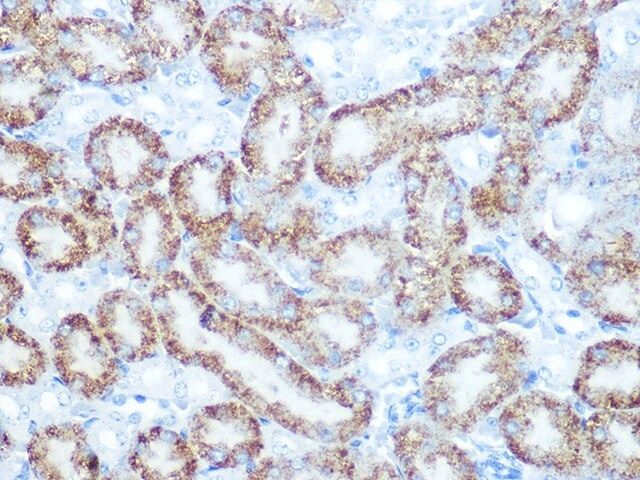

| technique(s) | immunofluorescence: 1:50-1:200 immunohistochemistry: 1:50-1:200 western blot: 1:500-1:2000 |